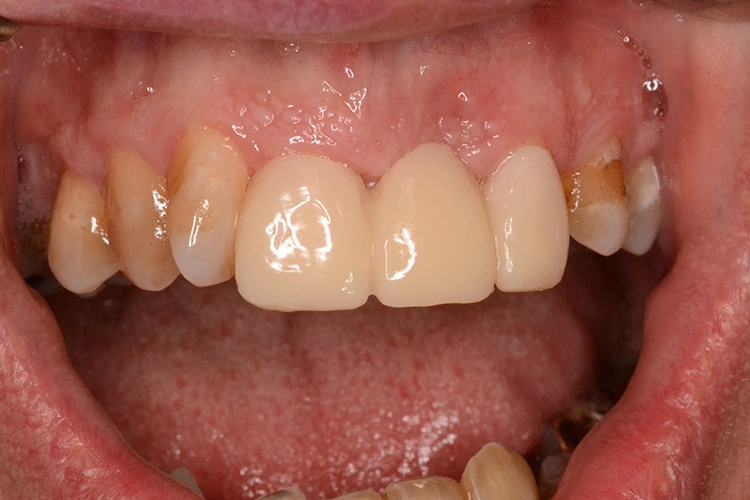

Bei diesem 49-jährigen, allgemeinanamnestisch unauffälligen Patienten liegen diverse ästhetisch störende Zahnstellungsanomalien vor, wobei Zahn 21 bei extremer Elongation frakturierte (Abb. 2a). Nach einer Übergangsversorgung mittels provisorischer Stiftkrone (Abb. 2b) entschied sich der Patient für eine Zahnentfernung bei gleichzeitiger Implantation. Im Ausgangs-DVT (Abb. 2c und d) zeigt sich im Cross-Sectional, wie weit der Processus alveolaris zurückliegt.